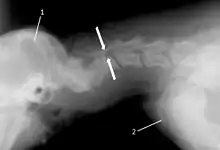

X-ray of wobbler disease in a dog

The disease tends to be gradually progressive. Symptoms such as weakness, ataxia, and dragging of the toes start in the rear legs. Dogs often have a crouching stance with a downward flexed neck. The disease progresses to the front legs, but the symptoms are less severe. Neck pain is sometimes seen. Symptoms are usually gradual in onset, but may progress rapidly following trauma.[6] X-rays may show misaligned vertebrae and narrow disk spaces, but it is not as effective as a myelogram, which reveals stenosis of the vertebral canal. Magnetic resonance imaging has been shown to be more effective at showing the location, nature, and severity of spinal cord compression than a myelogram.[7] Treatment is either medical to control the symptoms, usually with corticosteroids and cage rest, or surgical to correct the spinal cord compression. The prognosis is guarded in either case. Surgery may fully correct the problem, but it is technically difficult and relapses may occur. Types of surgery include ventral decompression of the spinal cord (ventral slot technique), dorsal decompression, and vertebral stabilization.[8] One study showed no significant advantage to any of the common spinal cord decompression procedures.[9] Another study showed that electroacupuncture may be a successful treatment for Wobbler disease.[10] A new surgical treatment using a proprietary medical device has been developed for dogs with disc-associated wobbler disease. It implants an artificial disc (cervical arthroplasty) in place of the affected disc space.[11]